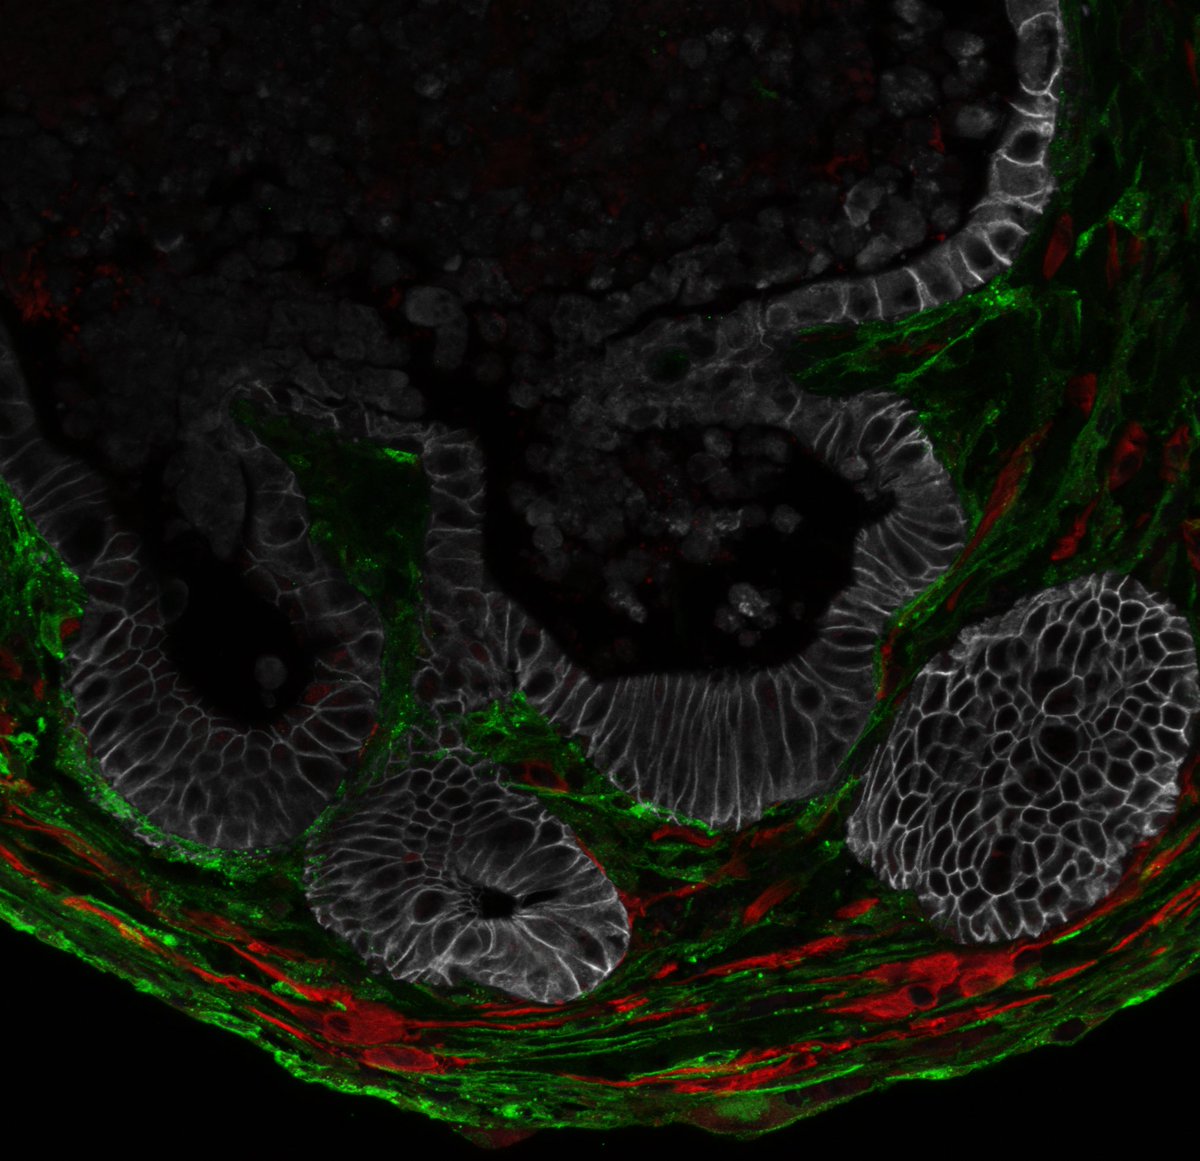

From embryo to adult and back again! In our latest preprint, we introduce oncoembryology—a parallel analysis of embryonic development and cancer. With my talented PhD student Tosca Dalessi, we explored the fascinating connections between these two processes. biorxiv.org/content/10.110…

Check out the latest preprint from our lab. Great work lead by Hassan Fazilaty and done mainly by Tosca Dalessi. Many thanks to all coauthors. I was privileged to help with this nice work a little bit. Classics as Krebs and Virchow were right.

Very happy to share our newest preprint! By leveraging embryonic development, we found that SoxC transcription factors are crucial drivers of colorectal cancer. Thanks Hassan Fazilaty for initiating and supervising this fascinating project!

Exciting new preprint from our lab led by Hassan Fazilaty and the PhD work of Tosca Dalessi, introducing #Oncoembryology!

Exciting new findings reveal eosinophils as key allies in the fight against colorectal cancer by blocking tumor spread. Great work by Kristina Handler, Deeksha Raju, Alessandra Gurtner & team lead by the amazing Isabelle Arnold Arnold_lab! Honored to be a part of this study. 👇